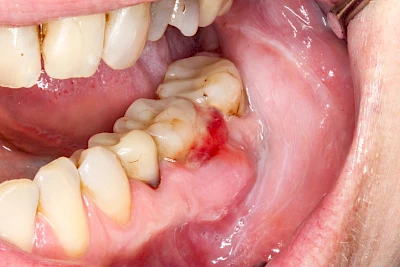

Sonderform: Schlupfwinkelinfektion

Im Laufe der menschlichen Entwicklung haben sich die Kiefer aufgrund unserer Nahrungsumstellung rückgebildet. Die Weisheitszähne haben daher oft keinen Platz mehr. Bei ca. 30 % der Menschen sind diese Zähne schon gar nicht mehr angelegt. Zum Teil liegen die Zähne versteckt (retiniert) im Kiefer und sind nicht sichtbar. Hin und wieder brechen die Zähne zwar durch die Schleimhaut, aber nicht vollständig – es handelt sich um einen erschwerten Zahndurchbruch (dentitio difficilis). Dann sind die Zähne noch teilweise bedeckt von einer "Schleimhautkapuze". Gehen hier Speisereste und Bakterien unter die Schleimhautkapuze kann sich eine sogenannte Schlupfwinkelinfektion bilden. Diese Entzündungen treten spontan auf, sind häufig sehr schmerzhaft und die Mundöffnung ist eingeschränkt. Hier ist umgehend der Zahnarzt zu kontaktieren.